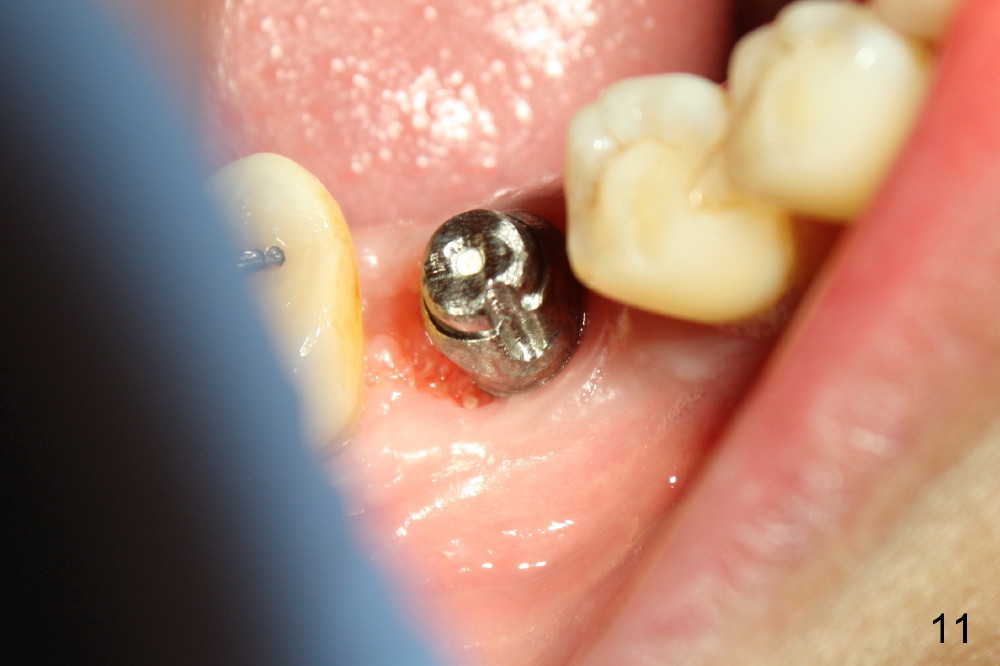

The infection may be related to chronic infection at the tooth #9. The latter is extracted, but the infection at the site of #30 does not resolve (Fig.5,6). The buccal flap is raised to reveal granulation tissue distobuccal to the implant (Fig.7). Bony defect and implant thread exposure are shown after debridement (Fig.8). Irradiated cancellous bone graft is placed to the defect (Fig. 9, Rocky Mountain Tissue Bank). The flap is closed with relative tension free. The definitive crown is temporarily cemented. The graft is exposed with no infection 2 week post grafting (Fig.10). The distobuccal defect appears to have healed 5 months post grafting (Fig.11) and the crown is permanently cemented (Fig.12). There is no buccal bone resorption, probably associated with immediate implantation. The patient remains asymptomatic 13 months postop.